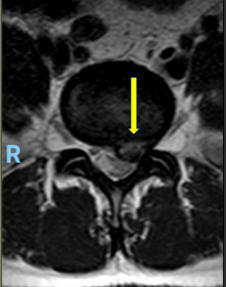

Hernia de disco lumbar extrusa L5 S1 (cortes axiales mostrando

gran compresión sobre la raíz nerviosa izquierda del segmento)

Hernia de disco lumbar extrusa L5 S1 (cortes axiales mostrando gran compresión sobre la raíz nerviosa izquierda del segmento)